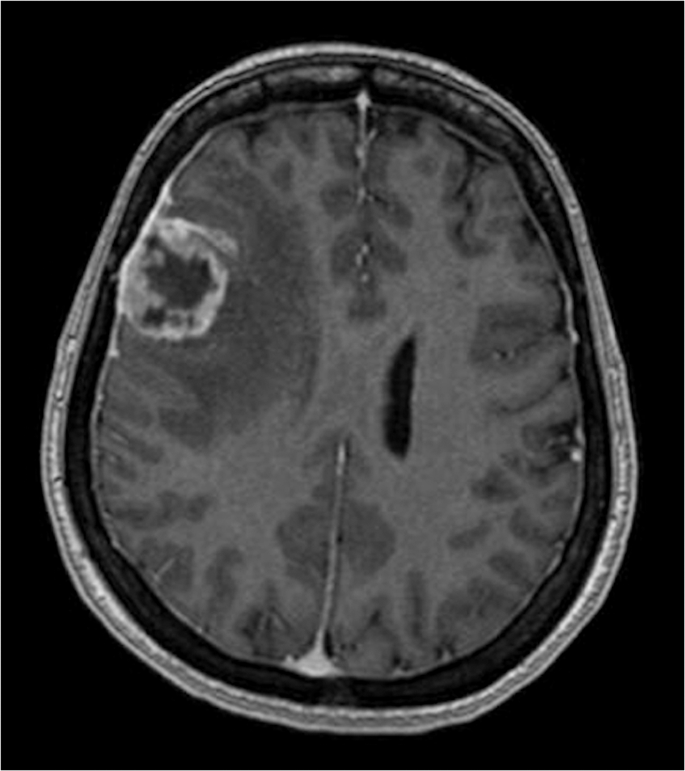

Examples of low and high complexity tumours, as assessed by the ANN, are illustrated in Figs. 4 and 5 respectively.